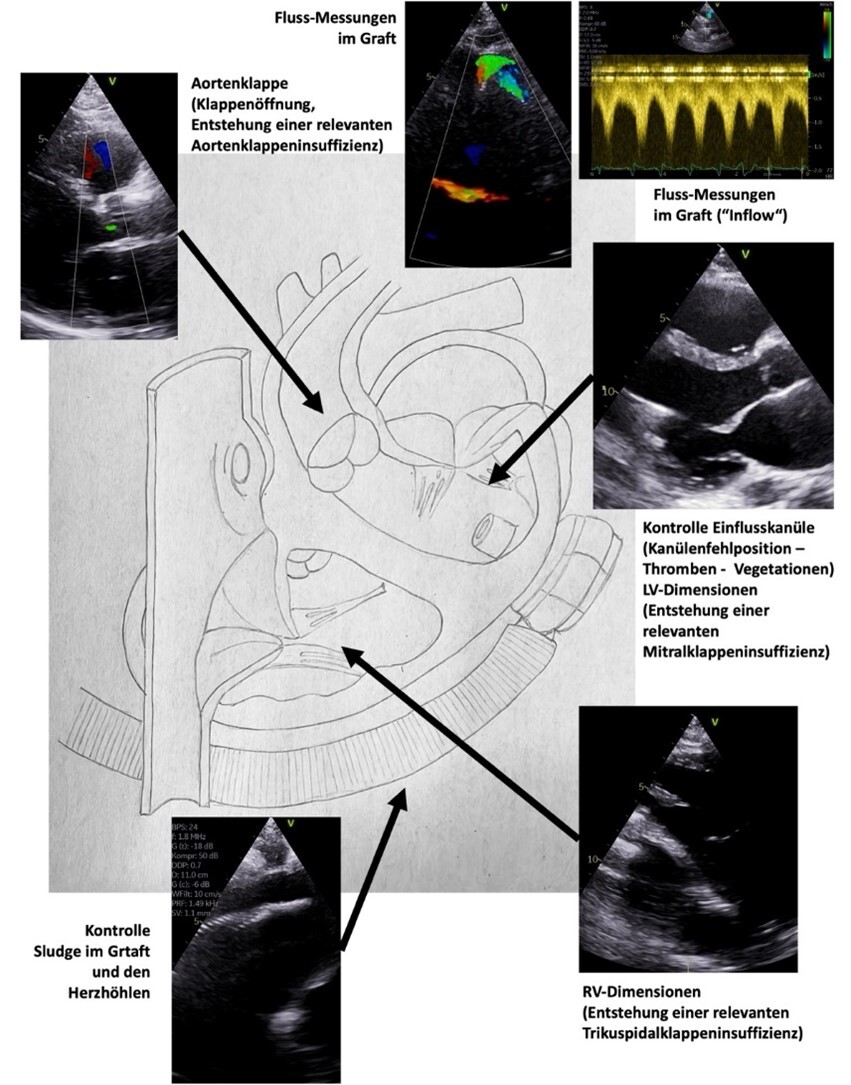

Zentrale Abbildungen aus dem Manual sind z. B. die Dokumentations-Protokolle mit der Kennzeichnung der Mindestanforderung durch „rote Punkte“ sowie die Anlotungen der echokardiographischen Kontrolle von LVAD-Systemen („left ventricular assist devices“):

qd-manual-echokardiographie-2

© DGK

Schemazeichnung zur echokardiographischen Kontrolle von LVAD-Systemen

Abb. 2: Schemazeichnung zur echokardiographischen Kontrolle von LVAD-Systemen („left ventricular assist devices“).